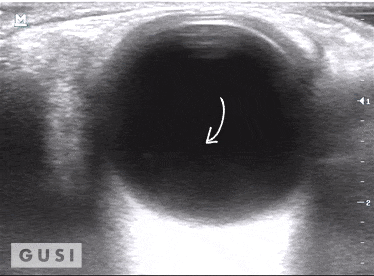

During the 2017 World Taekwondo Championships in Muju, Korea, a 30-year-old female athlete from Hong Kong was kicked in her left eye by an opponent. She reported fluctuating vision accompanied by pain during eye movement. A POCUS examination of the affected eye indicated a vitreous hemorrhage, with no evidence of lens subluxation or globe rupture.

On the ultrasound, as the athlete moved her eyes laterally, the hemorrhage (denoted by a white arrow) exhibited a swirling pattern within the globe, consistent with her eye movement. The athlete was promptly referred to a specialized medical center for an ophthalmology consultation, where the diagnosis of vitreous hemorrhage was confirmed. The patient was subsequently discharged from the Emergency Department with specific precautionary measures.